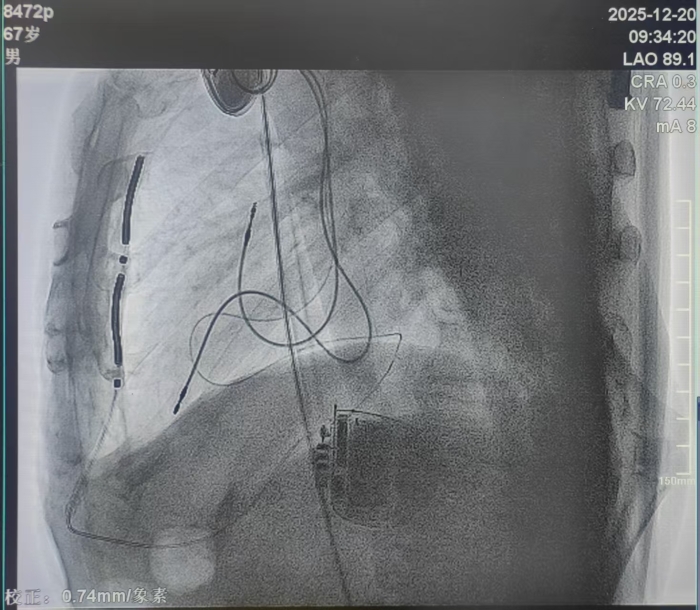

本例患者为67岁男性,7年前因患扩张型心肌病致心衰植入三腔起搏器(CRT-P),本次因室速晕厥入院,为心源性猝死的二级预防患者,需升级原起搏器为带有除颤功能的三腔起搏器(CRT-D)。但因患者上腔静脉闭锁,前期术中经多次尝试均无法经静脉植入除颤电极,为预防因恶性心律失常-室速、室颤导致患者晕厥及猝死,刘丽宏教授团队结合患者病情充分与患者及家属沟通后,为其选择植入EV-ICD血管外除颤器。团队在术前全面评估了原三腔起搏器的起搏感知功能良好,均为双极起搏状态;通过胸部CT认真评估患者解剖结构,审慎规划电极植入路径,并与心外科周钰峰主任及麻醉医师共同讨论手术操作细节,对术中可能遇到的问题进行了充分的讨论和准备,为患者制定了完善的手术方案。

△术中

胸骨下电极稳定,电学参数正常,原三腔起搏器工作状态未对EV-ICD的诊断治疗造成干扰,除颤测试通过,并同台更换了即将电池耗竭的原CRT-P起搏器。患者于手术次日由监护室转回普通病房即可下床活动,优化各项参数,患者恢复良好。